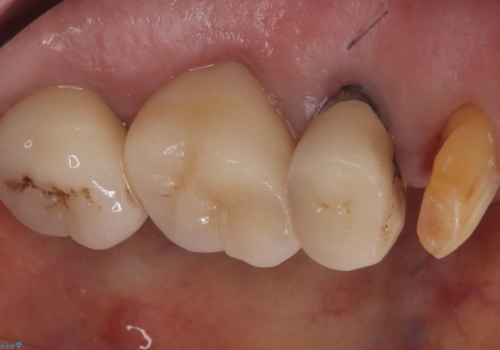

- 主訴:昔入れた被せものの境目の黒いところが気になる

クラウンの不適により境目に汚れが溜まり、黒く見えていました。

適合の良いクラウンへやり替えることとしました。